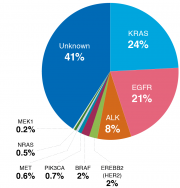

| 13:19, 16 בנובמבר 2017 | Alunbrig1.png (קובץ) |  |

73 קילו־בייטים | Motyk | 2 | |

| 12:15, 16 בנובמבר 2017 | Alunbrig3.png (קובץ) |  |

65 קילו־בייטים | Motyk | 1 | |

| 11:57, 16 בנובמבר 2017 | Alunbrig2.png (קובץ) |  |

1.63 מגה־בייטים | Motyk | 1 | |